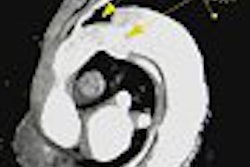

In another study, researchers from Brigham and Women's Hospital in Boston looked at 257 patients who presented with CAD symptoms and underwent cardiac MRI for assessment of myocardial viability or detection of myocardial infarction.

Over a mean follow-up of 13.8 months, there were 54 adverse events among the patients: 30 deaths, three acute MIs, and 21 cases of unstable angina or decompensated congestive heart failure. The presence of myocardial delayed enhancement on a contrast-enhanced MRI was the strongest predictor of those events, the researchers report.

Another group, composed primarily of researchers from the University of California at Irvine and other southern California centers, looked at infarct size in 100 patients. The patients were followed for an average of 25 months, and 15 died during that period.

The size of the infarction -- whether it was greater than 15% of the patient's left ventricular mass -- was the best independent predictor of death. Other variables, such as gender, extent of CAD, prior history of MI, hypertension, and diabetes weren't significant.

In the fourth study, researchers from Friedrich-Alexander-Universitaet Erlangen-Nürnberg in Erlangen, Germany, looked at 102 patients who had undergone reperfusion of an acute MI. Left ventricular dysfunction was determined by delayed contrast-enhanced MR within 10 days of the reperfusion.

Among the patients there were 11 deaths and reinfarctions over a mean follow-up of 2.5 years. Those adversely affected patients had significantly higher areas of dysfunction, as seen on MR, than those who were unaffected.

Ejection fraction and the dysfunctional-but-viable area as determined by MR were "related to occurrence of future events independent of the presence of risk factors for coronary arteriosclerosis," the researchers concluded.